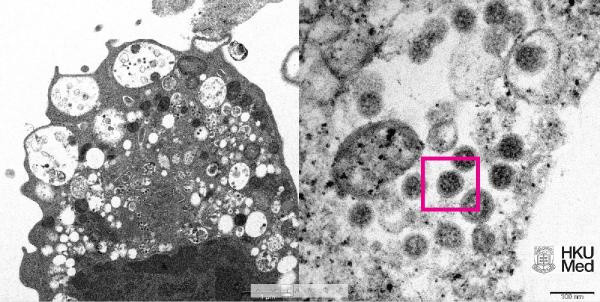

Abone olHKUMed’den yapılan açıklamada, araştırmacılar tarafından SARS-CoV-2 virüsünün Omicron varyantının elektron mikroskobu görüntüsünün ortaya çıkarıldığı belirtildi. Üniversite tarafından yayınlanan fotoğrafın solunda, küçük siyah viral partiküller içeren şişmiş veziküllerle hücre hasarını gösteren, SARS-CoV-2 Omicron varyantı ile enfeksiyondan sonra bir maymun böbrek hücresinin (Vero E6) düşük büyütmeli elektron mikrografının yer aldığı ifade edildi.

Fotoğrafın sağında ise yüzeylerinde korona şekilli sivri uçlara sahip viral partikül kümelerini gösteren enfekte bir Vero E6 hücresinin yüksek büyütmeli elektron mikrografının yer aldığı belirtildi.